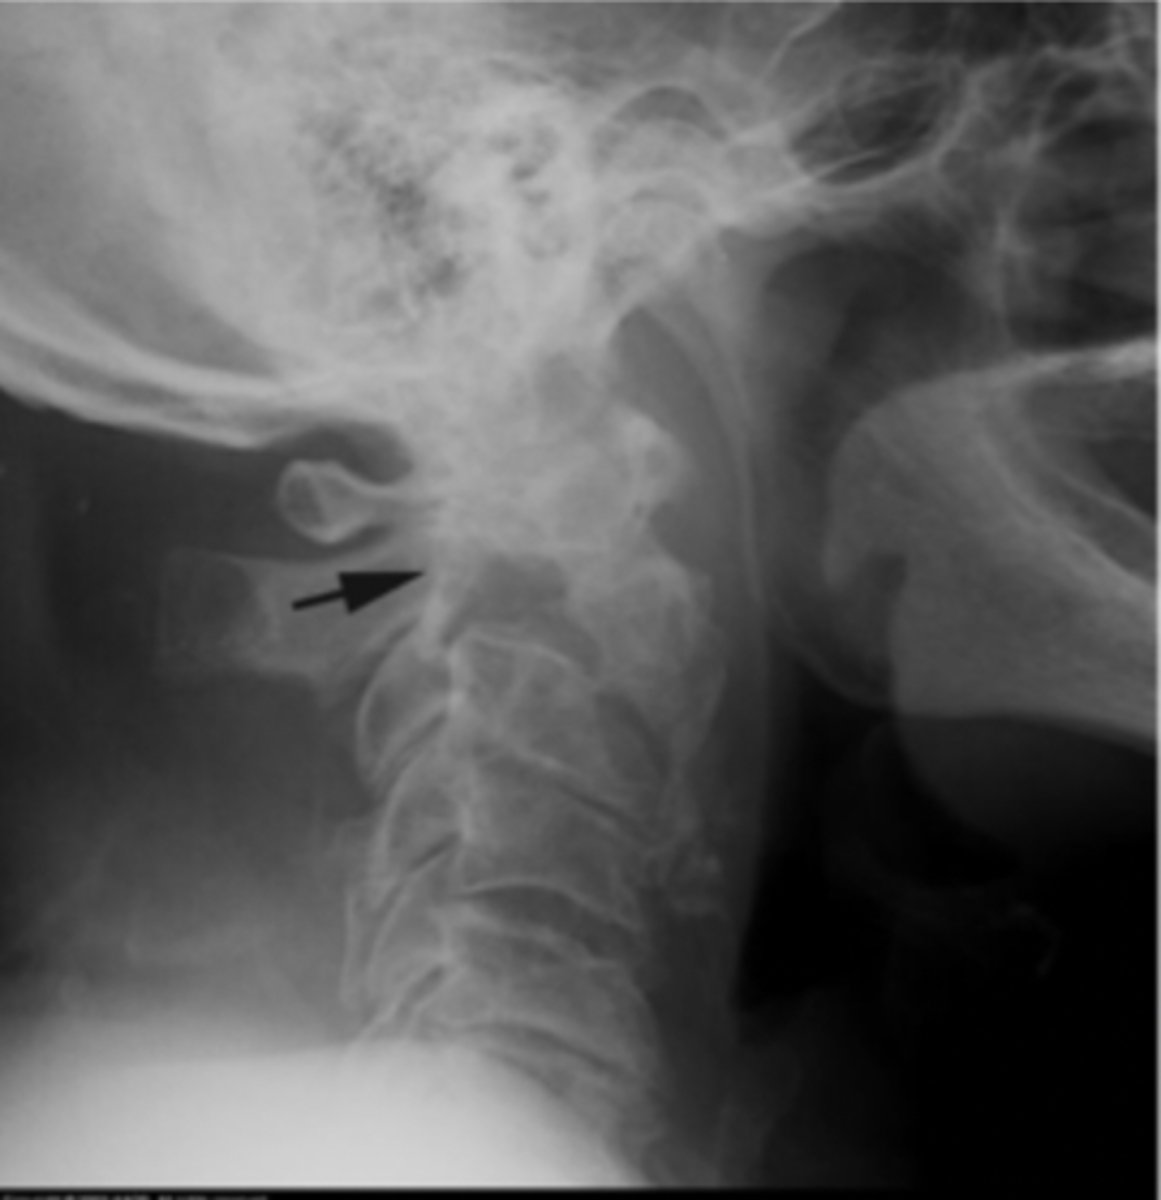

Lateral Cspine

What view is this?

Lateral Csp

Best for disc space and facet joint orientation